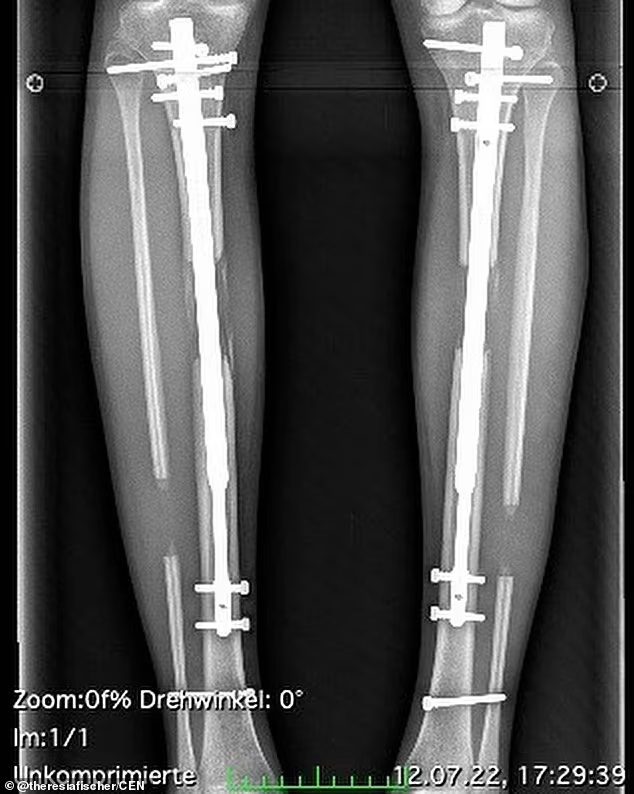

第一次手术,他的胫骨和腓骨被打断,然后挖空了胫骨内部,取出骨髓,再将一根钢杆放入骨头内(可伸缩),用螺钉将其固定。最后还要用钉子将骨头和外部的仪器固定。

手术后需要坐在轮椅上,而且每天都要进行痛苦的腿骨分离训练。

每天,布莱恩都要用扳手旋转腿部的固定器4次,试图将断开的骨头一点点分开。据介绍,这样硬生生将骨头分开的旋转,10次才能增加0.5毫米。

康复的时间长短因人而异,布莱恩花了2个多月的时间做复健。12月份手术,2月份才拆除固定器,结果他长高了约三英寸。